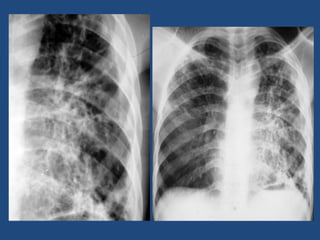

El documento habla sobre una actividad práctica de radiología cuyos objetivos son identificar diferentes estudios de radioimagen y explicar imágenes radiológicas en radiología convencional del sistema nervioso central y tórax. Menciona varias condiciones médicas como osteofitos, fracturas, artritis reumatoidea, osteoporosis, y diferentes tipos de calcificaciones que pueden verse en imágenes radiológicas.